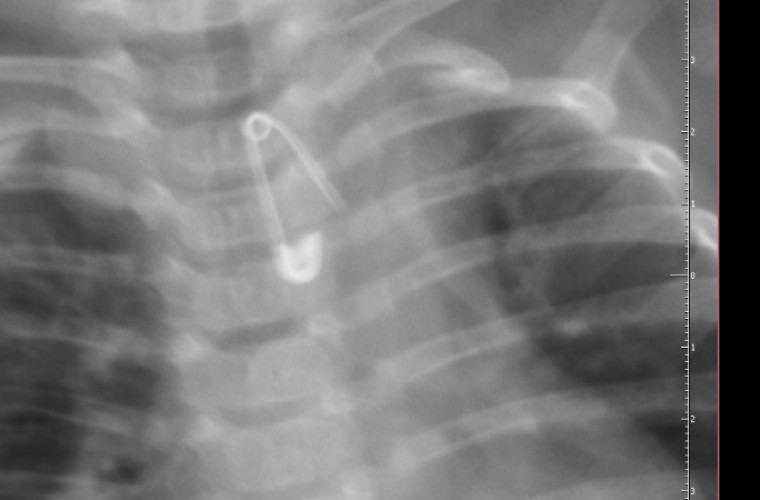

Rodzice z 6-miesięcznym Kubusiem natychmiast wsiedli w samochód i pojechali do szpitala w Krotoszynie. I choć - jak wykazało zdjęcie rentgenowskie - malec połknął 2-centymetrową agrafkę, która, rozwarta, skierowana była ostrzem w dół w przełyku chłopca - lekarka pełniąca dyżur w Szpitalnym Oddziale Ratunkowym w Krotoszynie kazała rodzicom zawieźć chłopca do szpitala w Ostrowie Wlkp. Chociaż w tym czasie na stanie były dwie karetki kazała im jechać własnym samochodem.

Na miejscu wykonano badanie RTG przełyku i jamy brzusznej, które potwierdziło obecność w przełyku ciała obcego. Po wykonaniu tego badania, pełniąca wówczas dyżur oskarżona lekarka, nie wykonując dalszej diagnostyki i nie zapoznając się z dokumentacją medyczną chłopca poleciła rodzicom przetransportowanie chłopca do Szpitala w Ostrowie Wielkopolskim ich prywatnym samochodem – tłumaczy Krzysztof Bukowiecki, rzecznik prasowy prokuratury regionalnej w Łodzi.